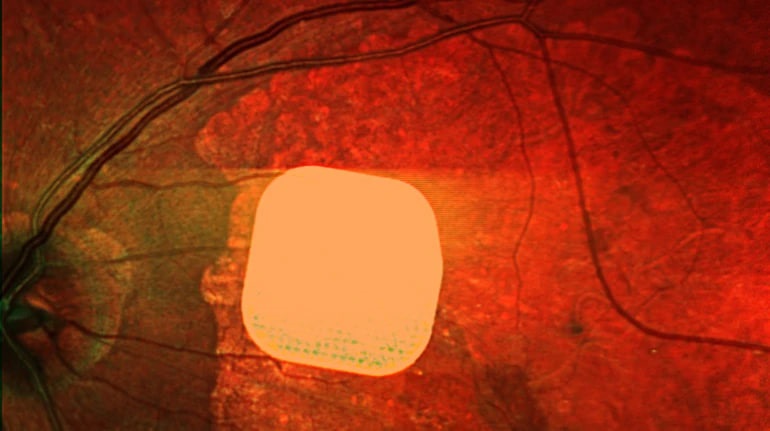

Британські лікарі успішно протестували новий електронний імплант Prima, який допомагає пацієнтам із віковою сліпотою, спричиненою макулодистрофією, частково відновити зір. Цей мікрочип розміром лише 2×2 міліметри встановлюють під сітківку ока пацієнта. Під час операції пацієнта під’єднують до системи окулярів доповненої реальності, яка допомагає передавати зображення на мікрочип і стимулювати клітини сітківки. Дослідження показало, що після імплантації 84% учасників змогли розрізняти літери, цифри та слова. Лікарі вважають, що ця технологія може стати великим кроком у розвитку штучного зору і допомогти людям з важкими зоровими порушеннями покращити якість життя.

Британські лікарі частково повернули зір пацієнтам за допомогою мікрочипа